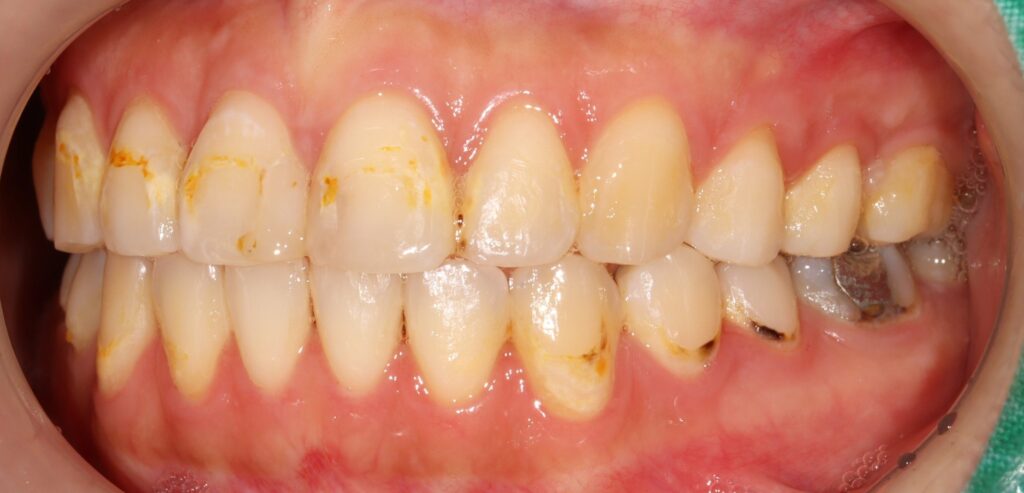

환자분께서는 교정치료 후

심미적 불만족으로 인해 광화문역치과인

본원에 내원해 주셨는데요.

치아 색상 불균형과 심미적 불만족을

주소로 구강 내 검진 결과,

상악 전치부에는 눈에 띄는 착색과 함께

치경부 우식이 다수 관찰되었으며,

일부 치아에서는 구조적인 손상까지

동반된 상태였습니다.